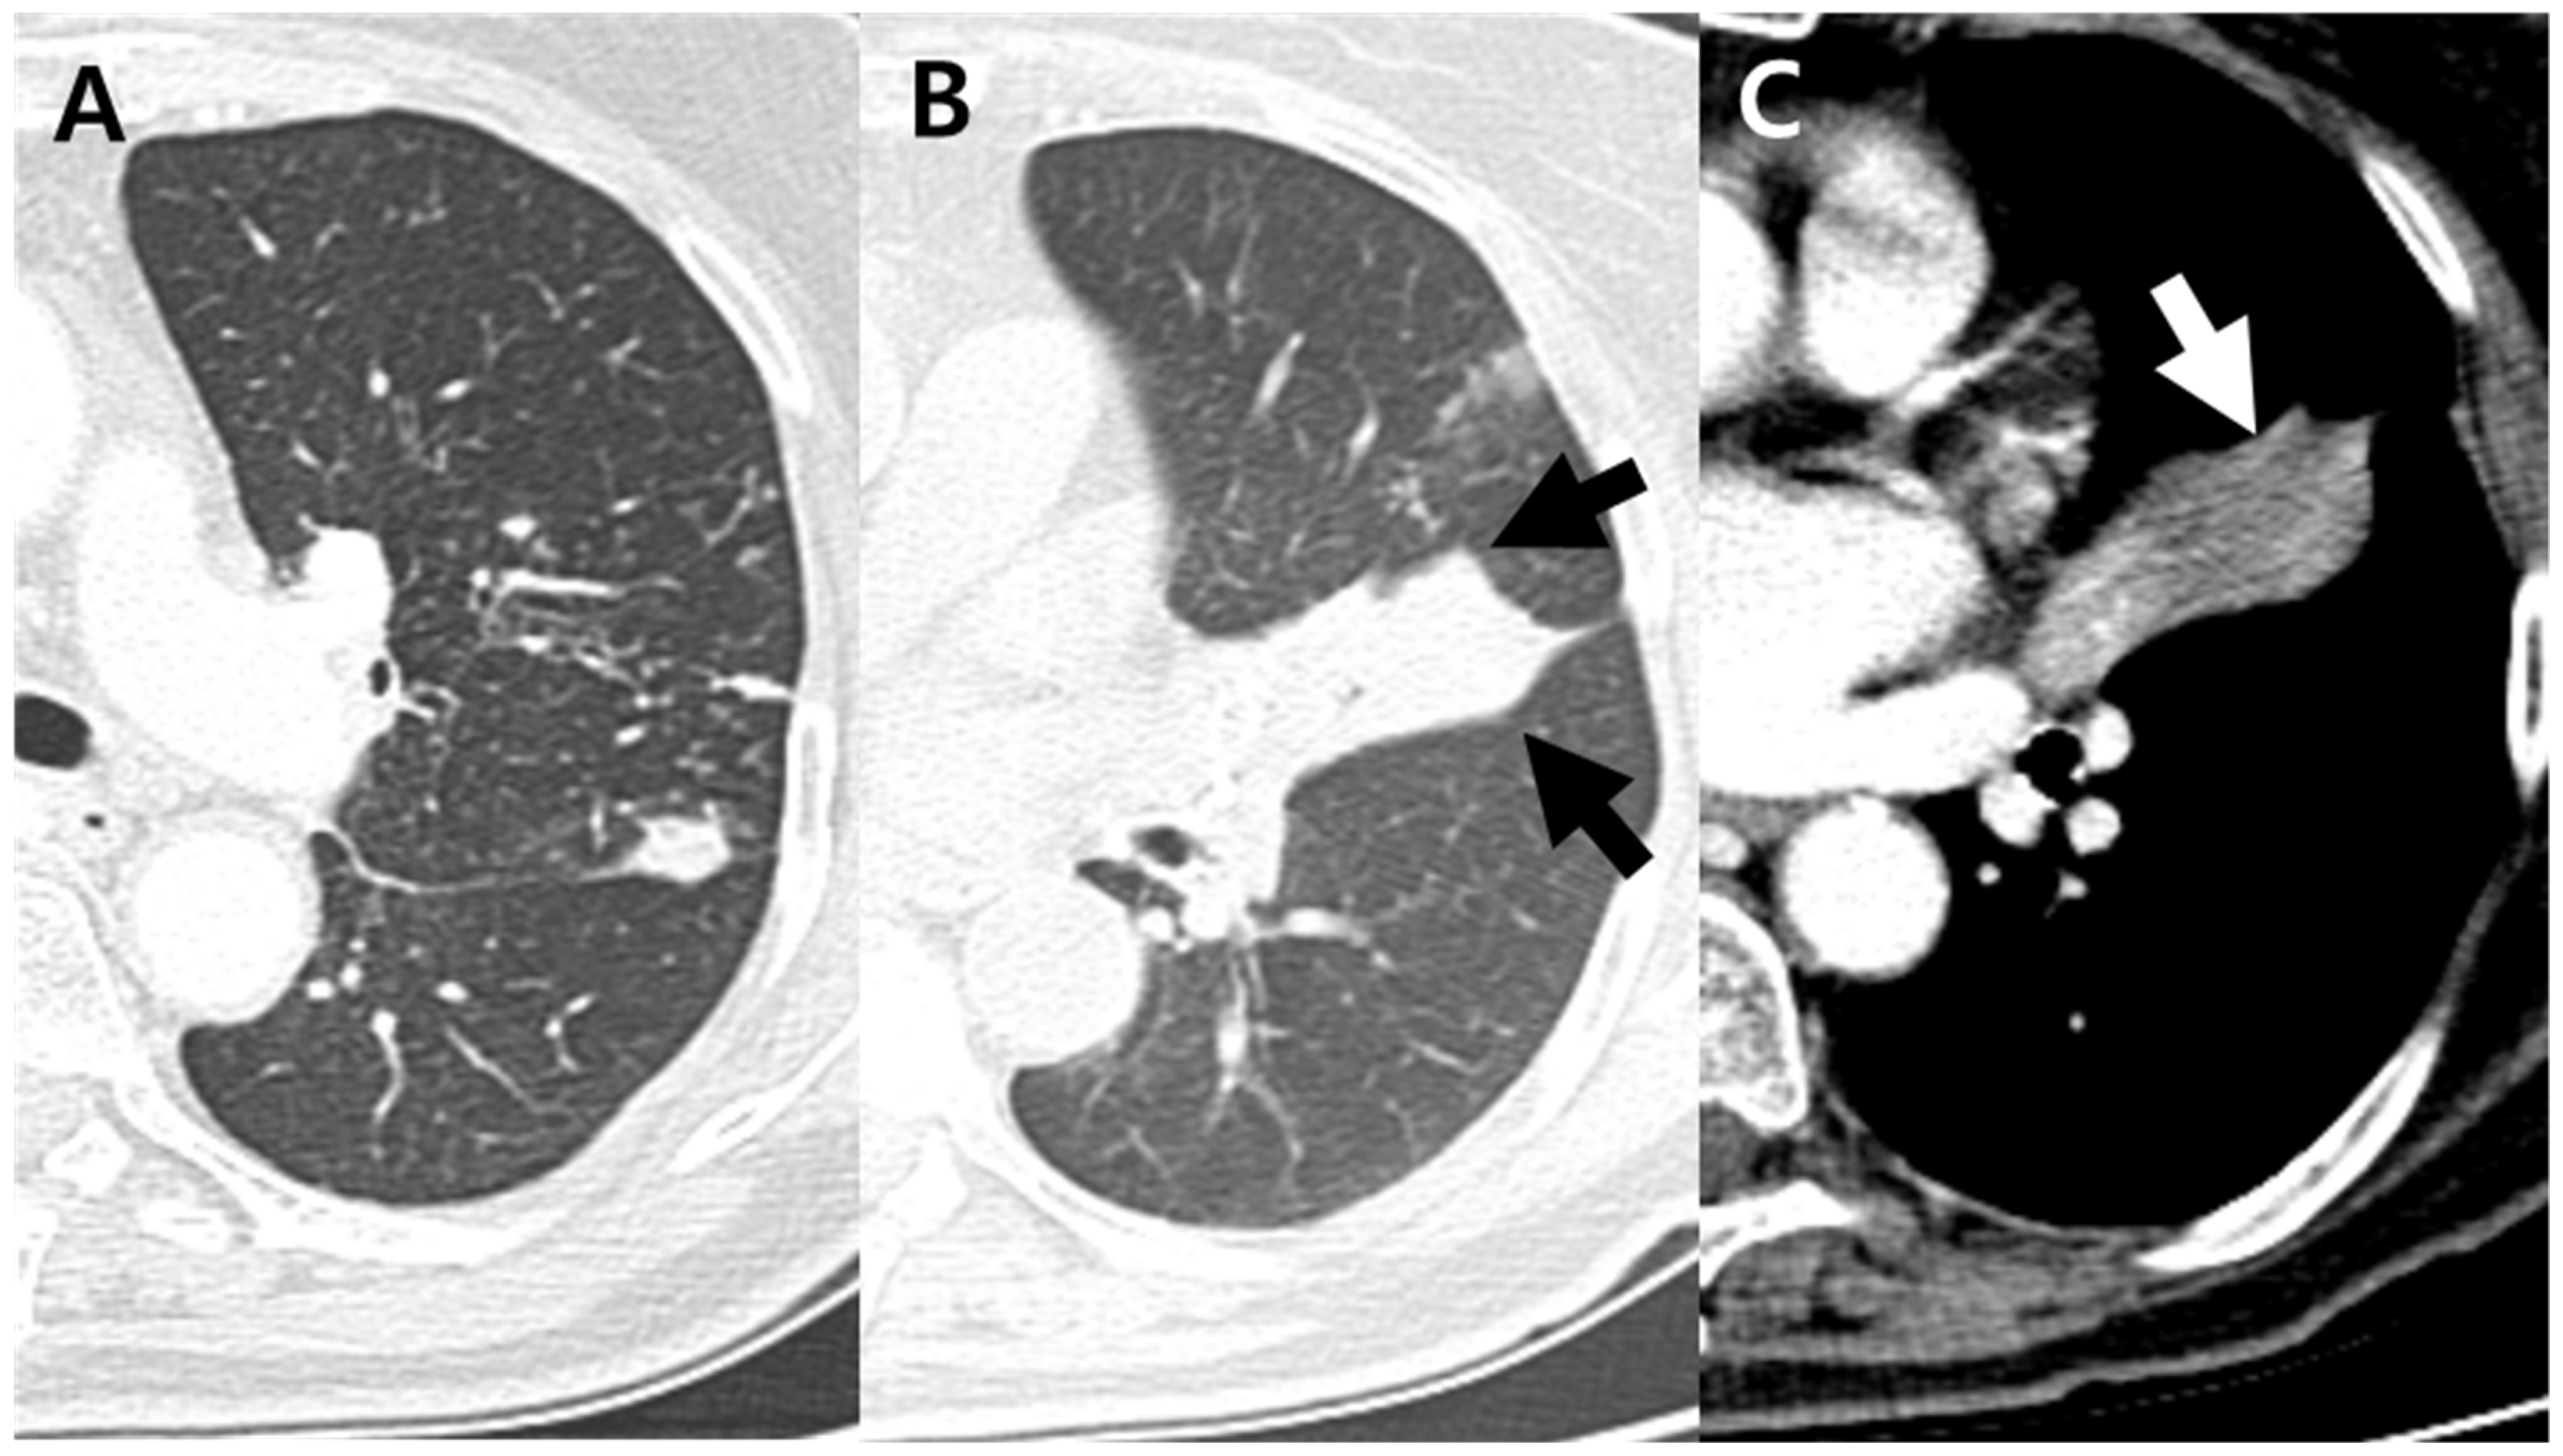

| Internal low-density area or focal contour bulge within atelectasis | 20 (10%) | 18 (64%) | 2 (1%) | <0.001 *** |